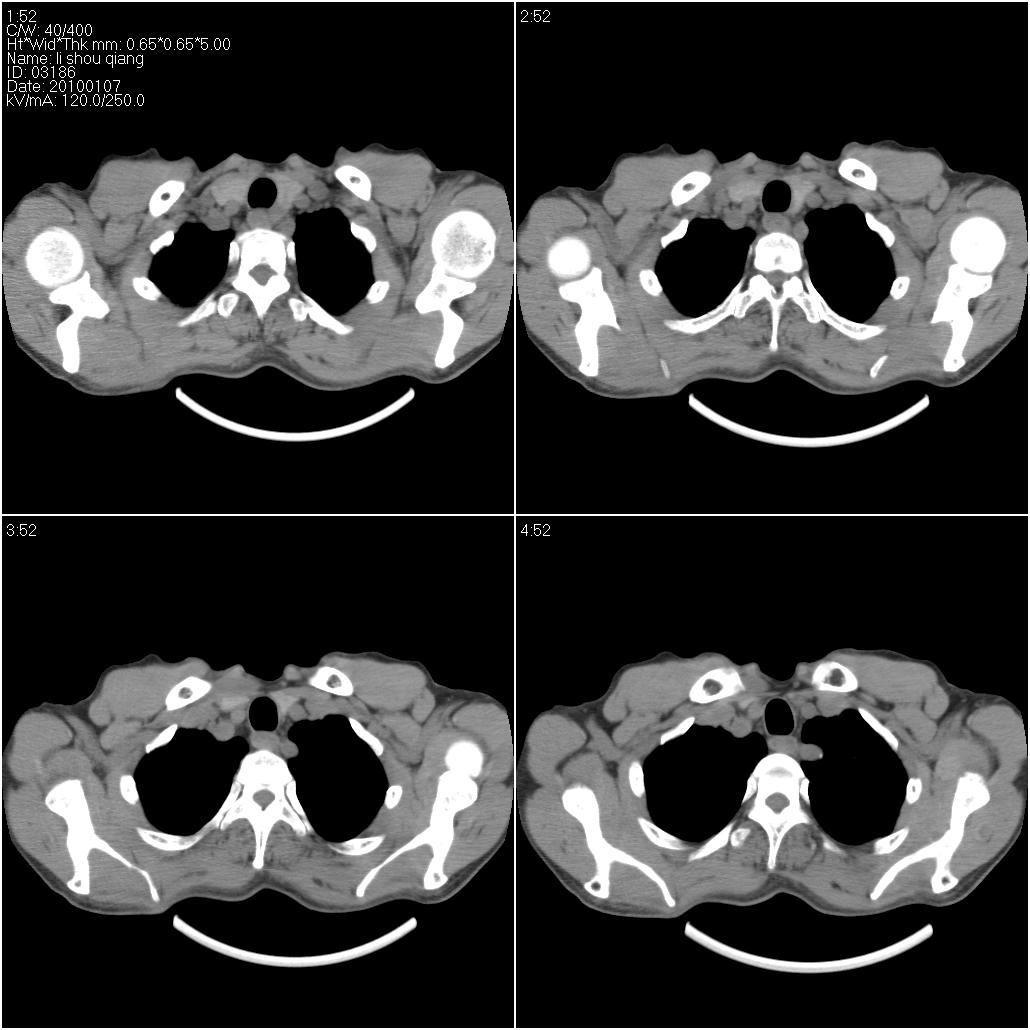

标题: CT24038:男性,58岁。主因咳嗽带血性CT检查。 [打印本页]

标题: CT24038:男性,58岁。主因咳嗽带血性CT检查。

右肺中叶外侧段见一不规则的软组织肿块,边缘可见毛刺,并见厚壁空洞,与胸膜分界欠清。另左下肺见多个小囊状扩张区